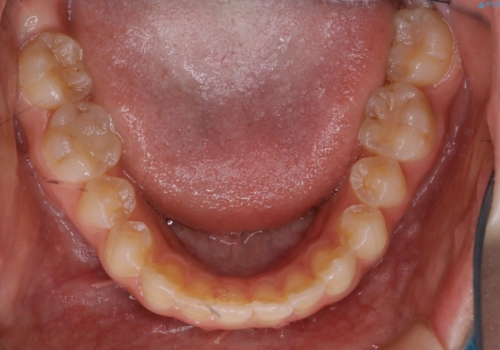

短期間ですきっ歯を改善:インビザラインLite

- 上の歯がすきっ歯なのと、歯が出ている気がするとご相談にいらした方です。

奥歯の噛み合わせに大きな問題がなく、患者様のご希望もあったため、前歯部メインで治療するインビザラインLiteで治療を行いました。

日常的に舌を突出する癖があったため、後戻り防止のために舌および口唇の筋機能訓練も合わせて行いました。

横顔のシルエットが改善し、口元もスッキリとなりました。